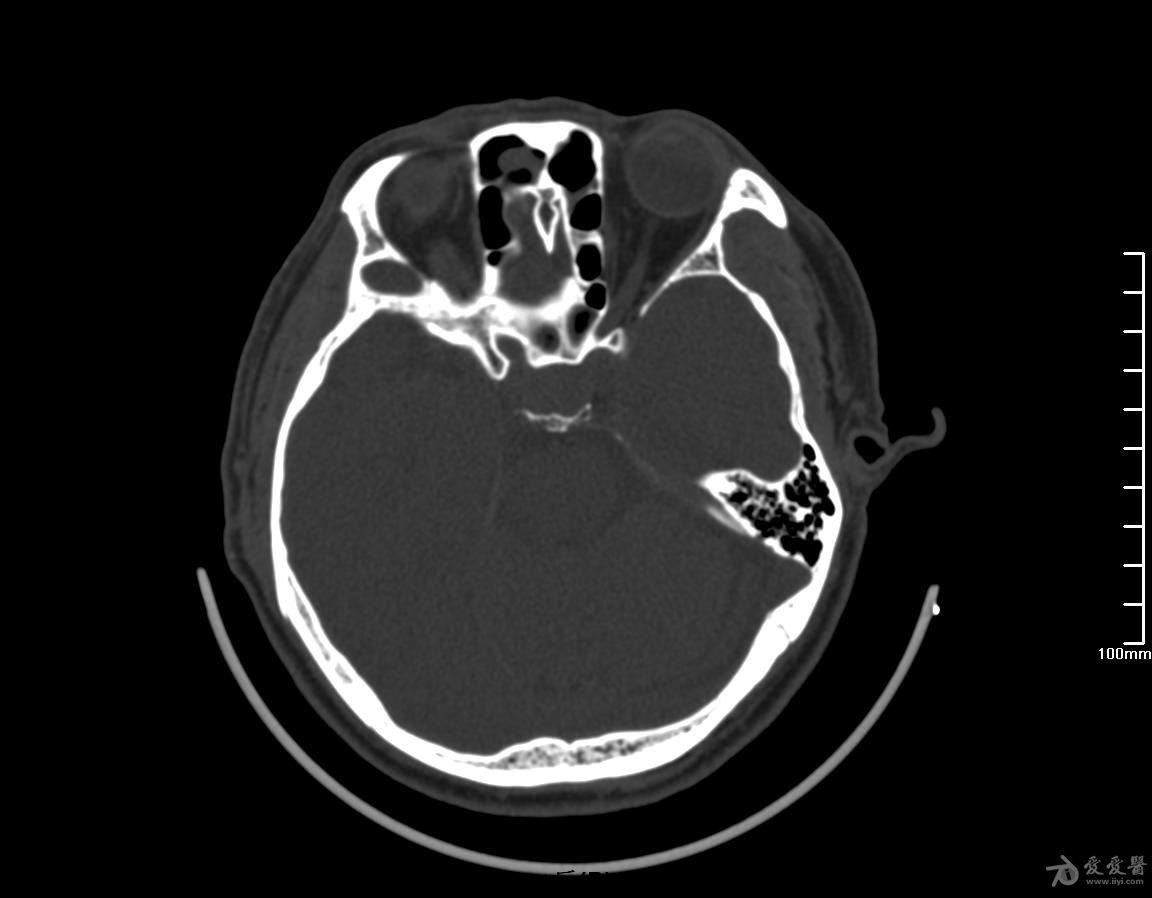

蝶鞍部占位穿刺术后复查